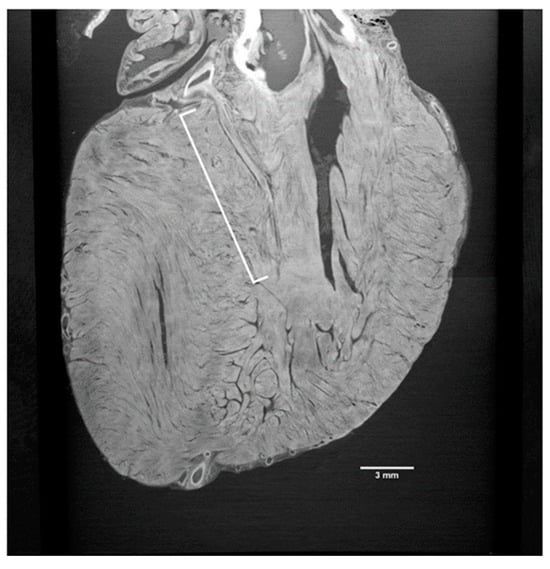

Indeed, Tsukube et al. [26] were able to resolve, with synchrotron radiation-based PhC microCT, the 3D morphology of various cardiovascular tissue samples, including the thoracic aorta, ductus arteriosus, and cardiac conduction system. In particular, PhC microCT showed differences in 3D structures of the tunica media in an aortic dissection, 3D morphological changes in the transition from the ductus arteriosus to the descending aorta in a surgically excised sample of coarctation of the aorta, and it was also useful for examining abnormalities of the cardiac conduction system in congenital heart defects (Figure 2).

Figure 2.

X-ray phase-contrast tomography image displaying the initial septal branch of the left anterior descending artery (LAD); here, a two-dimensional depiction of the heart is captured from a distinct angle. The image distinctly showcases the section of the first septal branch (highlighted by the white bracket) stemming from the LAD (CC-BY 4.0) [26].